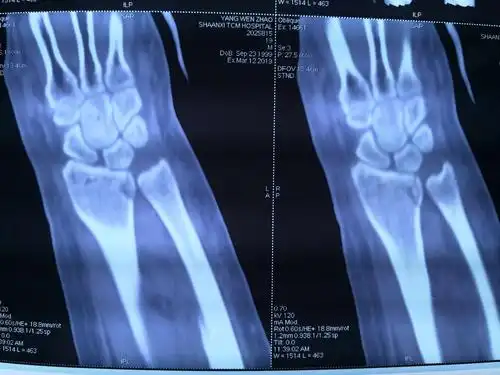

右桡骨远端骨折

扩大fcr入路治疗复杂桡骨远端骨折

尺桡骨远端双骨折,小孩,7岁

"令人感动的桡骨远端骨折复位"后续

ct可见桡骨头骨折软骨面塌陷明显

桡骨头骨折

活动受限,在外院行拍片及ct检查后就诊于我院 临床诊断:左桡骨颈骨折